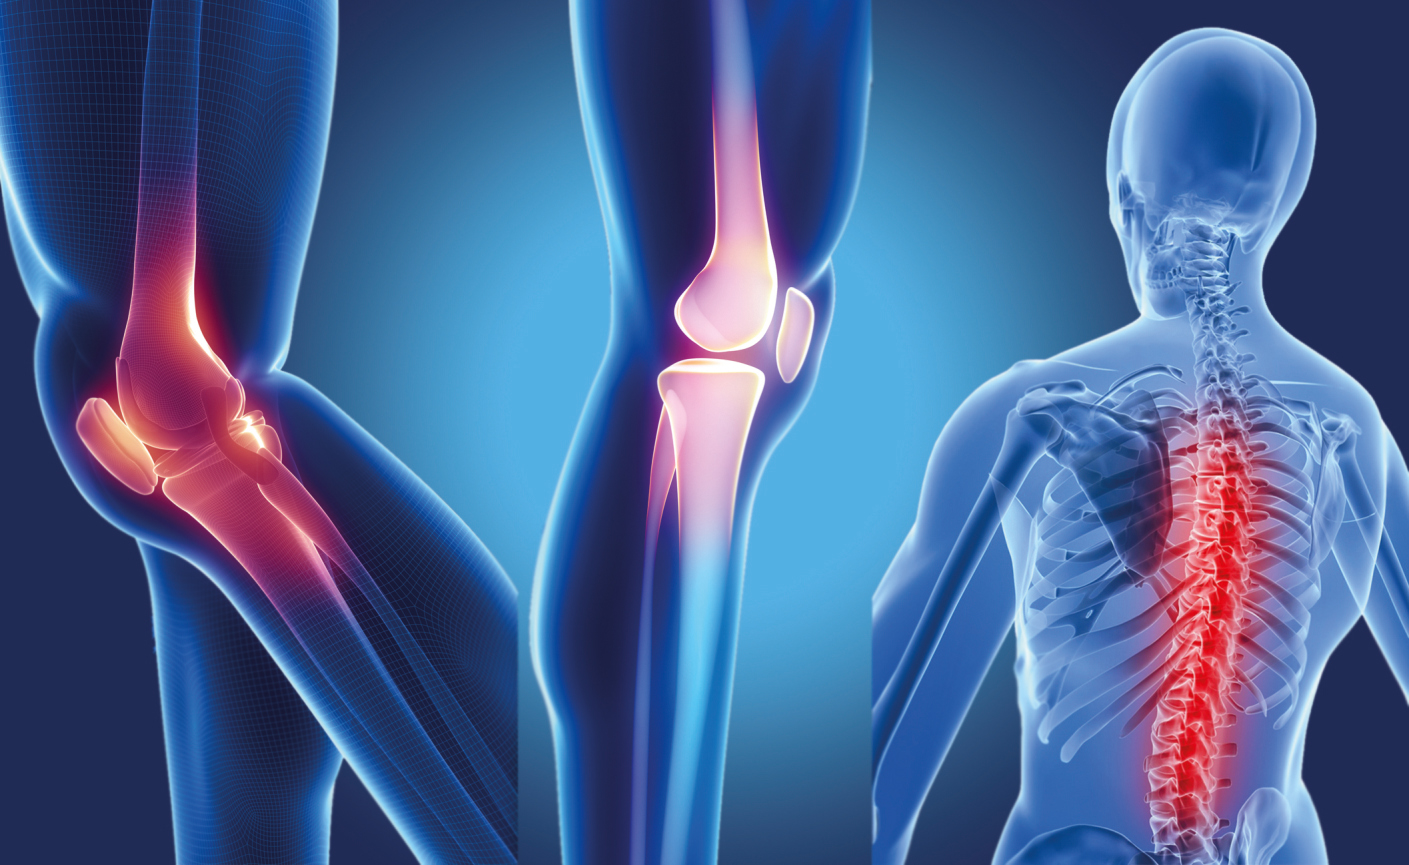

Анатомические рисунки суставов человека